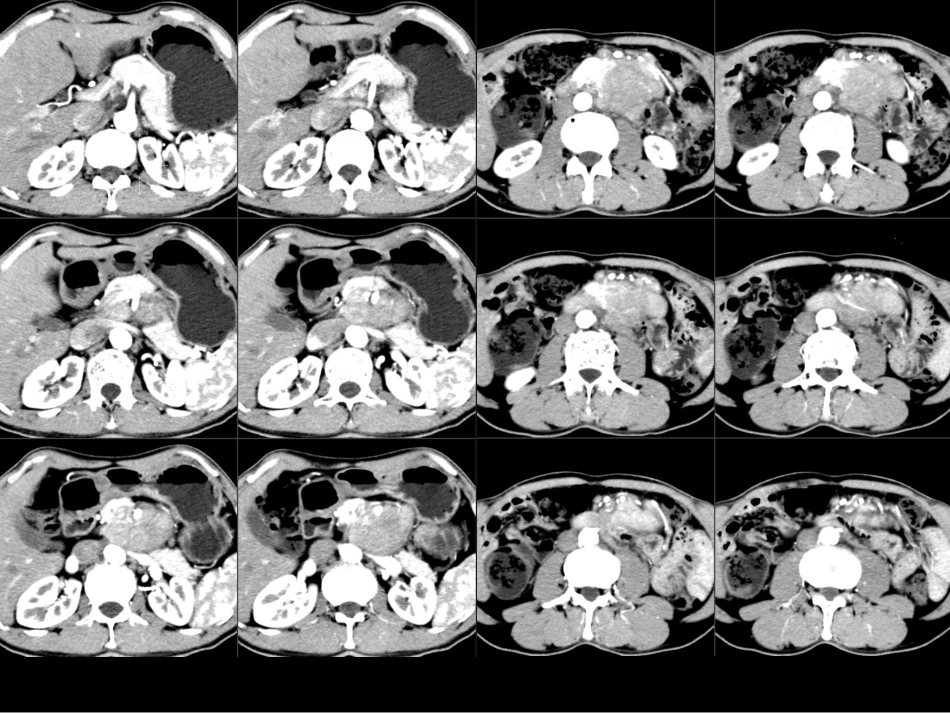

病例1病例2病例3Castleman病CT表现小讲座福建医科大学附属第一医院影像科孙辉红(sunhvhong@sina.com)病例1•男,58岁,反复左上腹胀痛半年余。肿瘤标志物正常•*1甲胎蛋白(AFP)1.5800-13.6ng/ml电化学发光法•*2癌胚抗原(CEA)2.10-5.2(吸烟者:0-6.5)ng/ml电化学发光法•3糖类抗原125(CA125)5.7600-35U/ml电化学发光法•4糖类抗原15-3(CA15-3)10.2300-25U/ml电化学发光法•5糖类抗原19-9(CA19-9)1.4200-34U/ml电化学发光法•6糖类抗原72-4(CA72-4)•淀粉酶(AMYL)>35632bg32-641U/L干化学强生诊断及鉴别诊断征象:平扫密度均匀,无出血、坏死、钙化。增强:动脉期明显强化,门脉期及实质期均匀持续强化。周围情况:胰腺、十二指肠、血管诊断??•定位:胰腺、腹腹后•定性:富血供肿瘤•胰腺神经内分泌肿瘤•副神经节肿瘤(嗜铬细胞瘤)•间质瘤•恶性淋巴瘤•透明血管型Castleman(巨淋巴结增生症)病例1:男,58岁CT0372461B1.(腹膜后淋巴结)Castleman病伴累及胰腺组织,胰腺腺泡破坏伴嗜酸性变,部分淋巴滤泡增生活跃。2.(另送小肠一段)Castleman病累及肠壁浆膜层及肌层,病变周围肠壁肌层间血管扩张,似血管瘤样表现,小肠上、下切端未见明显病变。免疫组化:CD34、SMA、D2-40:血管(+);CD3、CD20、Ki-67、CD10、Bcl-2、Bcl-6:表达模式未见显著异常;CD38浆细胞(+)。胰头区见巨大占位,约8.2cm×6.8cm,病灶境界尚清,可见分叶,边缘见点状钙化,密度不均匀,增强后呈明显不均匀强化,胰腺头部部分消失。胰管和胆管均不扩张,胰体部胰管旁尚可见一0.6cm左右小囊状低密度灶。十二指肠向右侧推移。胰头部占位,考虑神经内分泌肿瘤,胰体部小囊肿(胰十二指肠切除标本)恶性间质瘤.梭形细胞型,细胞略丰富,轻到中度异型,散在异型明显的细胞,局灶区查见肌层浸润和粘膜浸润,核分裂约0-1个/50HPF,形态学提示为低度恶性间质瘤,切缘未见肿瘤累及.胃旁淋巴结4枚,未见肿瘤转移.建议检测基因突变状况.酶标((09-N5752):CK广(-),VIM(100%++),SMA(10%+),DES(-),Ki-67(小于1%+),CD117(100%++),DOG-1(100%++),CD34(100%+),Nestin(100%+),DES(-),VEGF(-),VEGFR1(-),VEGFR2(-),VEGFR3(+/-),S100(70%+).恶性间质瘤胰头后方占位,考虑为十二指肠来源间质瘤可能大,胰尾占位,考虑导管内乳头状粘液瘤可能大,胰尾MT伴后腹膜淋巴结转移不能完全除外右后腹膜巨大肿瘤,位于十二指肠、胰头后方,与下腔静脉,左右肾静脉、肝动脉、门静脉、胆管关系密切,直径约15厘米。作Koch切口翻起十二指肠,暴露肿瘤右侧及下侧部分,打开小网膜孔,分离肿瘤和肝动脉、门静脉、胆管之间粘连及交通小血管。分离肿瘤和十二指肠、胰头之间粘连及交通小血管,肿瘤根部位于下腔静脉,左肾静脉之间,予完整切除。术中触动肿瘤,患者血压一度升高至200mmHg以上,切除肿瘤后血压至正常水平,为安全起见,患者送ICU继续治疗。冰冻病理为副神经节瘤。(胰头)镜下肿瘤组织呈腺泡样巢状排列,结合酶标,考虑副神经节瘤伴部分区细胞丰富,细胞轻度异型,纤维包膜内个别脉管可见瘤栓,建议临床密切随访。酶标(2010-N4391):CD56(+),SYN(-),CHG(+),S100(+),CD10(-),VIM(+),B-cat(+),KI67(-),CK广(-),Keratin(-),ACTH(-),VIP(-),GLV(-),GS(-),SENO(-),Insnlin(-),PP(-),Some(-),EGFR(-)。副神经节瘤Castleman病(Castleman’sdisease,CD)•又称巨淋巴结增生症或血管淋巴性滤泡组织增生,是一种罕见的以不明原因淋巴结肿大为特征的慢性淋巴组织增生性疾病.•临床上按肿大淋巴结的分布分为单中心型(UCD)和多中心型(MCD)。•病理学按组织学特征分为透明血管型(hyaline-vasculartype,HVT)、浆细胞型(plasmacelltype,PCT)和兼有二者特征的混合型。CD临床分型•CD是一种少见的良性淋巴结增生性疾病。病因不明,可能与慢性炎性反应、免疫功能异常等因素有关。•CD按组织病理学标准分为HV型和PC型•HV型占75%~90%,PC型占10%~25%,混合型占1%~4%。病理表现•透明血管型CD镜下表现为淋巴滤泡增生伴生发中心形成,大量小...